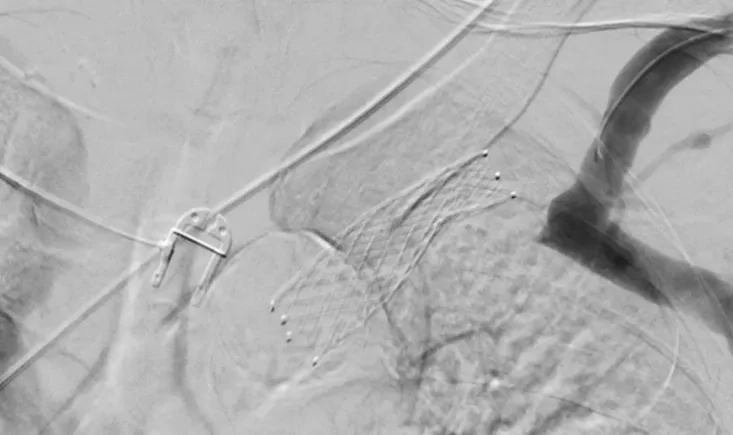

An 80-year-old patient faces a recurrent type II endoleak after EVAR, with his aneurysm sac continuing to g…